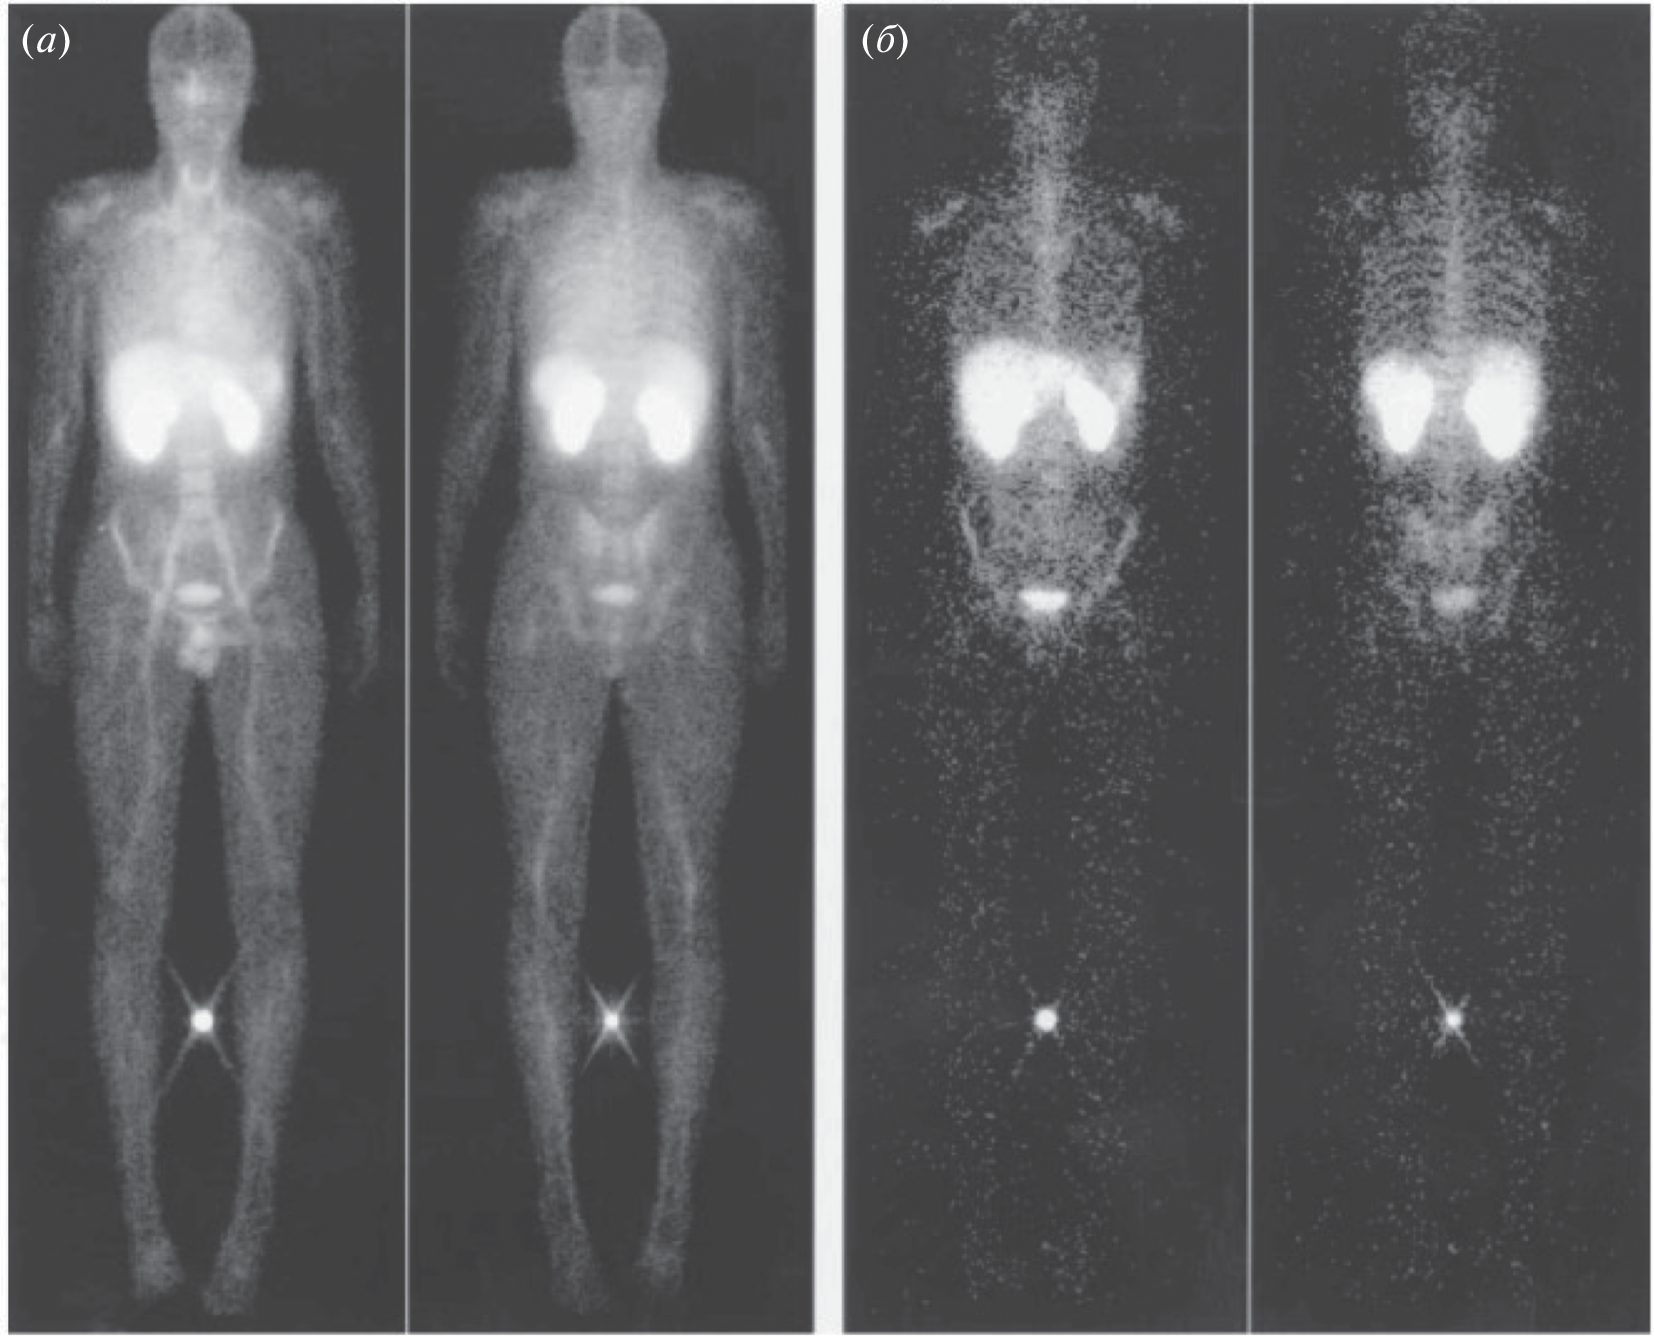

- Kemerink G.J., Liu X., Kieffer D., Ceyssens S., Mortelmans L., Verbruggen A.M, Steinmetz N.D., Vanderheyden J.-L., Green A.M., Verbeke K. // J. Nuclear Med. 2003. V. 44. P. 947–952.